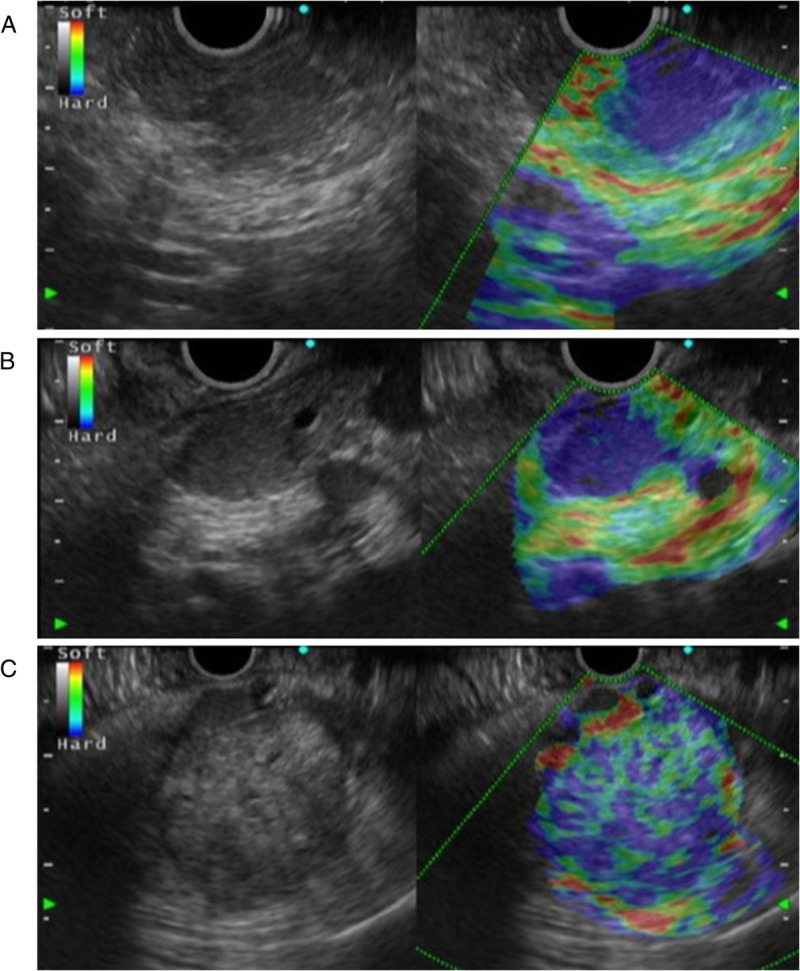

Contrast-enhanced harmonic EUS with time-intensity curve analysis useful for diagnosis of pancreatic metastasis from renal cell carcinoma (with videos).

对比增强谐波 EUS 与时间强度曲线分析有助于诊断肾细胞癌的胰腺转移(附视频)。